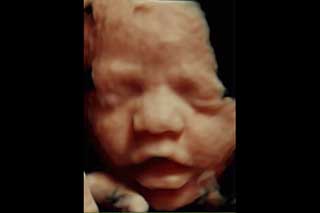

La evaluación 3D se basa en la obtención de imágenes 3D de algunas partes fetales, especialmente el rostro.

Ultrasonido en 3D

Reconstrucción digital de imágenes para formar una sola imagen en 3 dimensiones (3D), permitiendo así poder visualizar el rostro de su bebé.

La ecografía 3D es aquella que permite a usted ver la superficie corporal de su bebé, esto permite observar detalles como: labios, nariz, pómulos, frente, manos, entre otras.

Para lograr esto es necesario que se cumplan muchas condiciones como por ejemplo que el bebé no este mirando hacia atrás, que la placenta, el cordón o las extremidades no le tapen su rostro, así como que el líquido amniótico esté en cantidad suficiente.